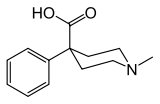

Ketobemidones

Structures